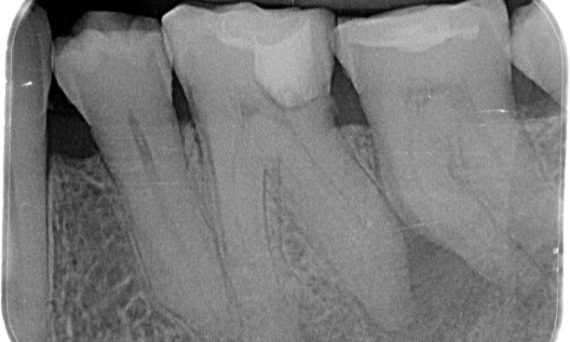

Before: Periapical radiolucency associated primarily with the distal root and loss of lamina dura on the mesial root.

After: TruNatomy was chosen in this case to allow a caries leveraged approach and a focus on pericervical dentin preservation especially on the mesial aspect where the tooth had a more minimal restoration.

Bath, UK